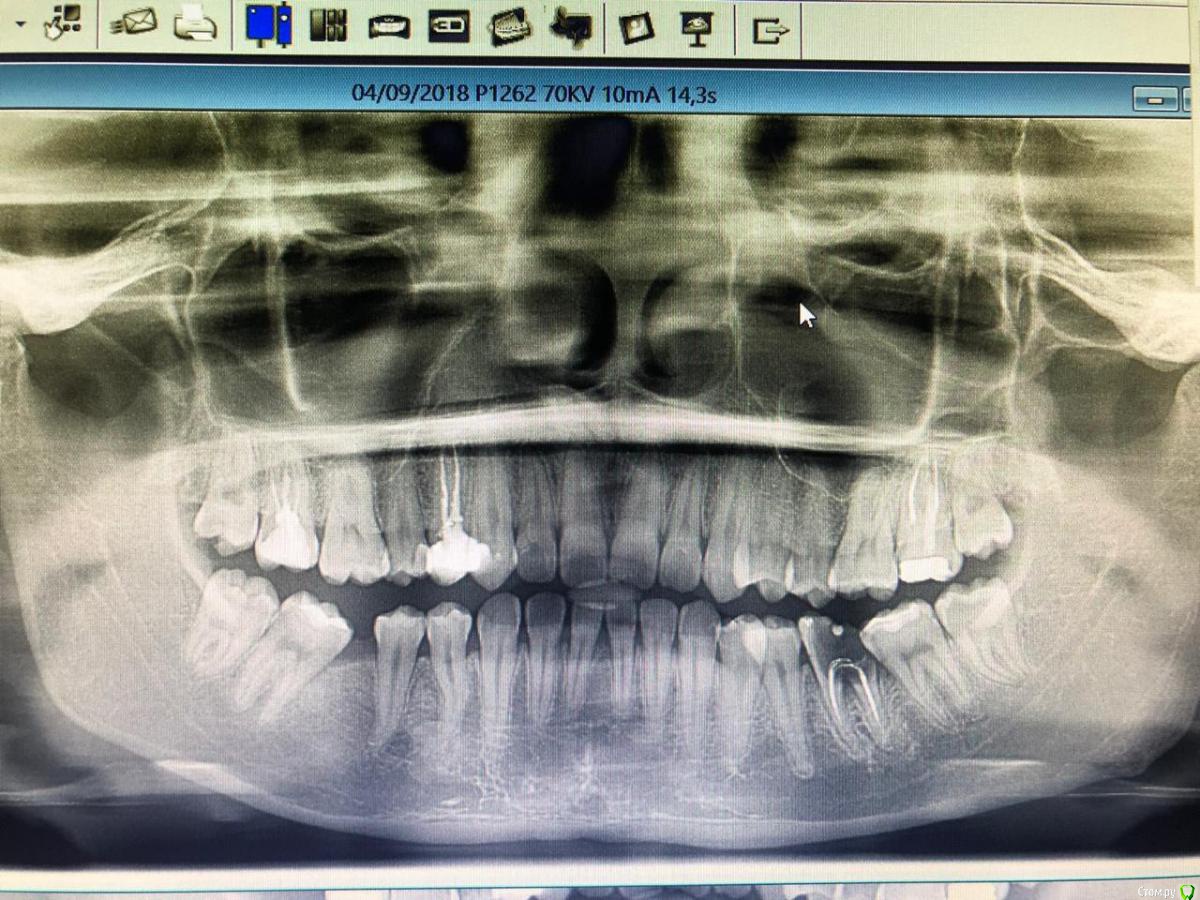

Daniyar Опубликовано 12 февраля, 2019 Поделиться Опубликовано 12 февраля, 2019 FYI 4 Ссылка на комментарий

Daniyar Опубликовано 12 февраля, 2019 Поделиться Опубликовано 12 февраля, 2019 (изменено) Спасибо Данияр за рассказ , ждем снимки , очень интересно . P\S: вы им точно 8ки реплантировали ? ( шутка, не обижайтесь - не смог удержаться)))) Да смешно.Док, я не собирался Вам что-то доказывать. Тем более указывать на действия. Я просто предложил Вам как вариант. Такой же, как и ваша гемисекция. Каждый выбирает, то что у него работает.А я сделал, так как я сделал, потому что хотел по-пробывать. Пациент ничего не теряет, все делал бесплатно.П/с вариант с болтом всегда естьВсе коллега, думаю удовлетворил ваш интерес. Удачи с вашей 8 койАссалам Уалейкум Изменено 12 февраля, 2019 пользователем Daniyar 1 Ссылка на комментарий

___49___ Опубликовано 12 февраля, 2019 Автор Поделиться Опубликовано 12 февраля, 2019 (изменено) Что касается Злой 8ки , убрал с гемисекцией . Изменено 12 февраля, 2019 пользователем ___49___ Ссылка на комментарий